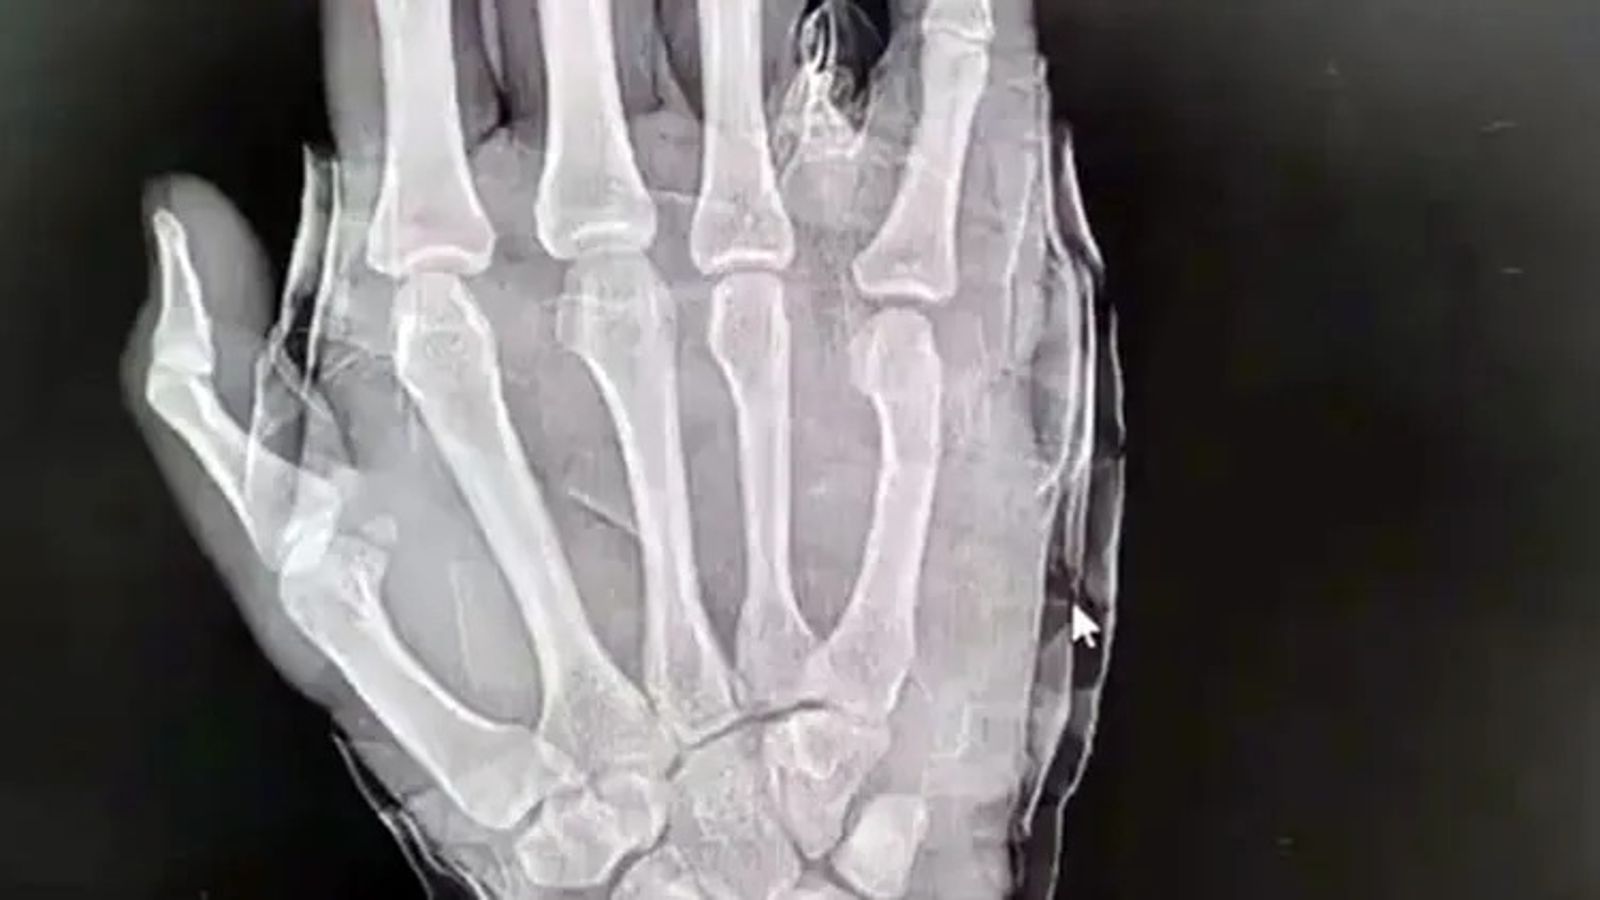

醫師進一步拍X光片後,表示李男右手第五掌骨頸骨折,且斷端移位,評估後為其進行手法整復,醫師也提醒李男,「不要總以為你的拳頭很硬,其實它有時挺脆弱的。」李男則尷尬表示,「以後再也不敢隨便發脾氣了。」